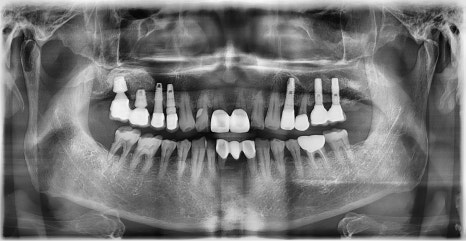

대치동 임플란트

위 엑스레이 사진과 같이 오른쪽 아래 어금니를 발치한 후 인공치근을 식립한 과정을 1차 수술이라고 합니다. 다른 부위에 식립한 임플란트와는 달리 치아의 뿌리에 해당하는 픽스쳐만 식립되어 있는 것을 확인할 수 있습니다. 이 인공치근이 잇몸뼈와 충분히 유착될 때까지 잇몸 아래 묻어두어서 안정적인 골유착을 유도합니다.

이 때 환자분의 잇몸뼈 상태나 식립한 임플란트 픽스쳐의 초기 고정 상태 등을 고려합니다. 환자의 잇몸뼈의 상태가 좋지 않거나 감염이 우려되는 경우, 또는 픽스쳐의 초기 고정력이 약한 경우, 어떠한 외부의 자극이 가해지지 않도록 커버 스크류라고 하는 작은 나사 뚜껑을 덮어서 잇몸 안에 픽스쳐를 묻어두어 골유착이 일어날 때까지 충분히 기다립니다. 추후 보철물을 연결하기 위해 잇몸 안에 묻어둔 임플란트 픽스쳐를 외부로 노출시키는 과정이 필요한데 이 과정이 바로 2차 수술에 해당합니다.